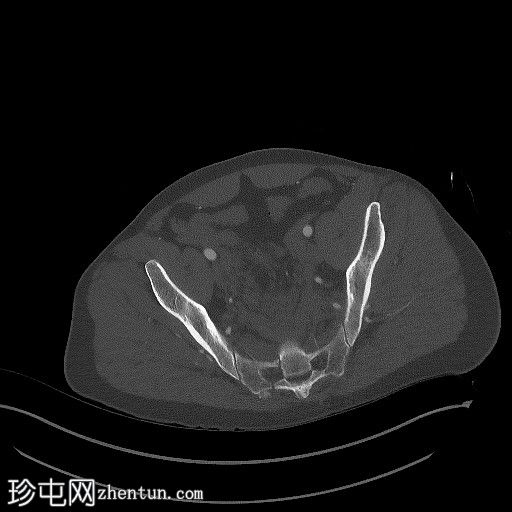

2.jpg

右侧骶骨斜形粉碎性骨折伴移位导致广泛的腹膜后血肿,血肿延伸至主动脉分叉处。未见动脉显影或造影剂聚集,提示无活动性出血。骨折从第一骶椎椎体延伸至右侧骶骨翼,并累及右侧椎板。骶前间隙可见粉碎性骨折碎片。

左侧后髂骨轻度移位骨折,骨折线从髂嵴延伸至骶髂关节。骶髂关节对位正常。尾骨脱位并向左侧移位。盆底肌肉扭曲并向左侧移位,但其他方面看似完整。

左侧耻骨上下支粉碎性骨折。髋臼和耻骨联合未受累。